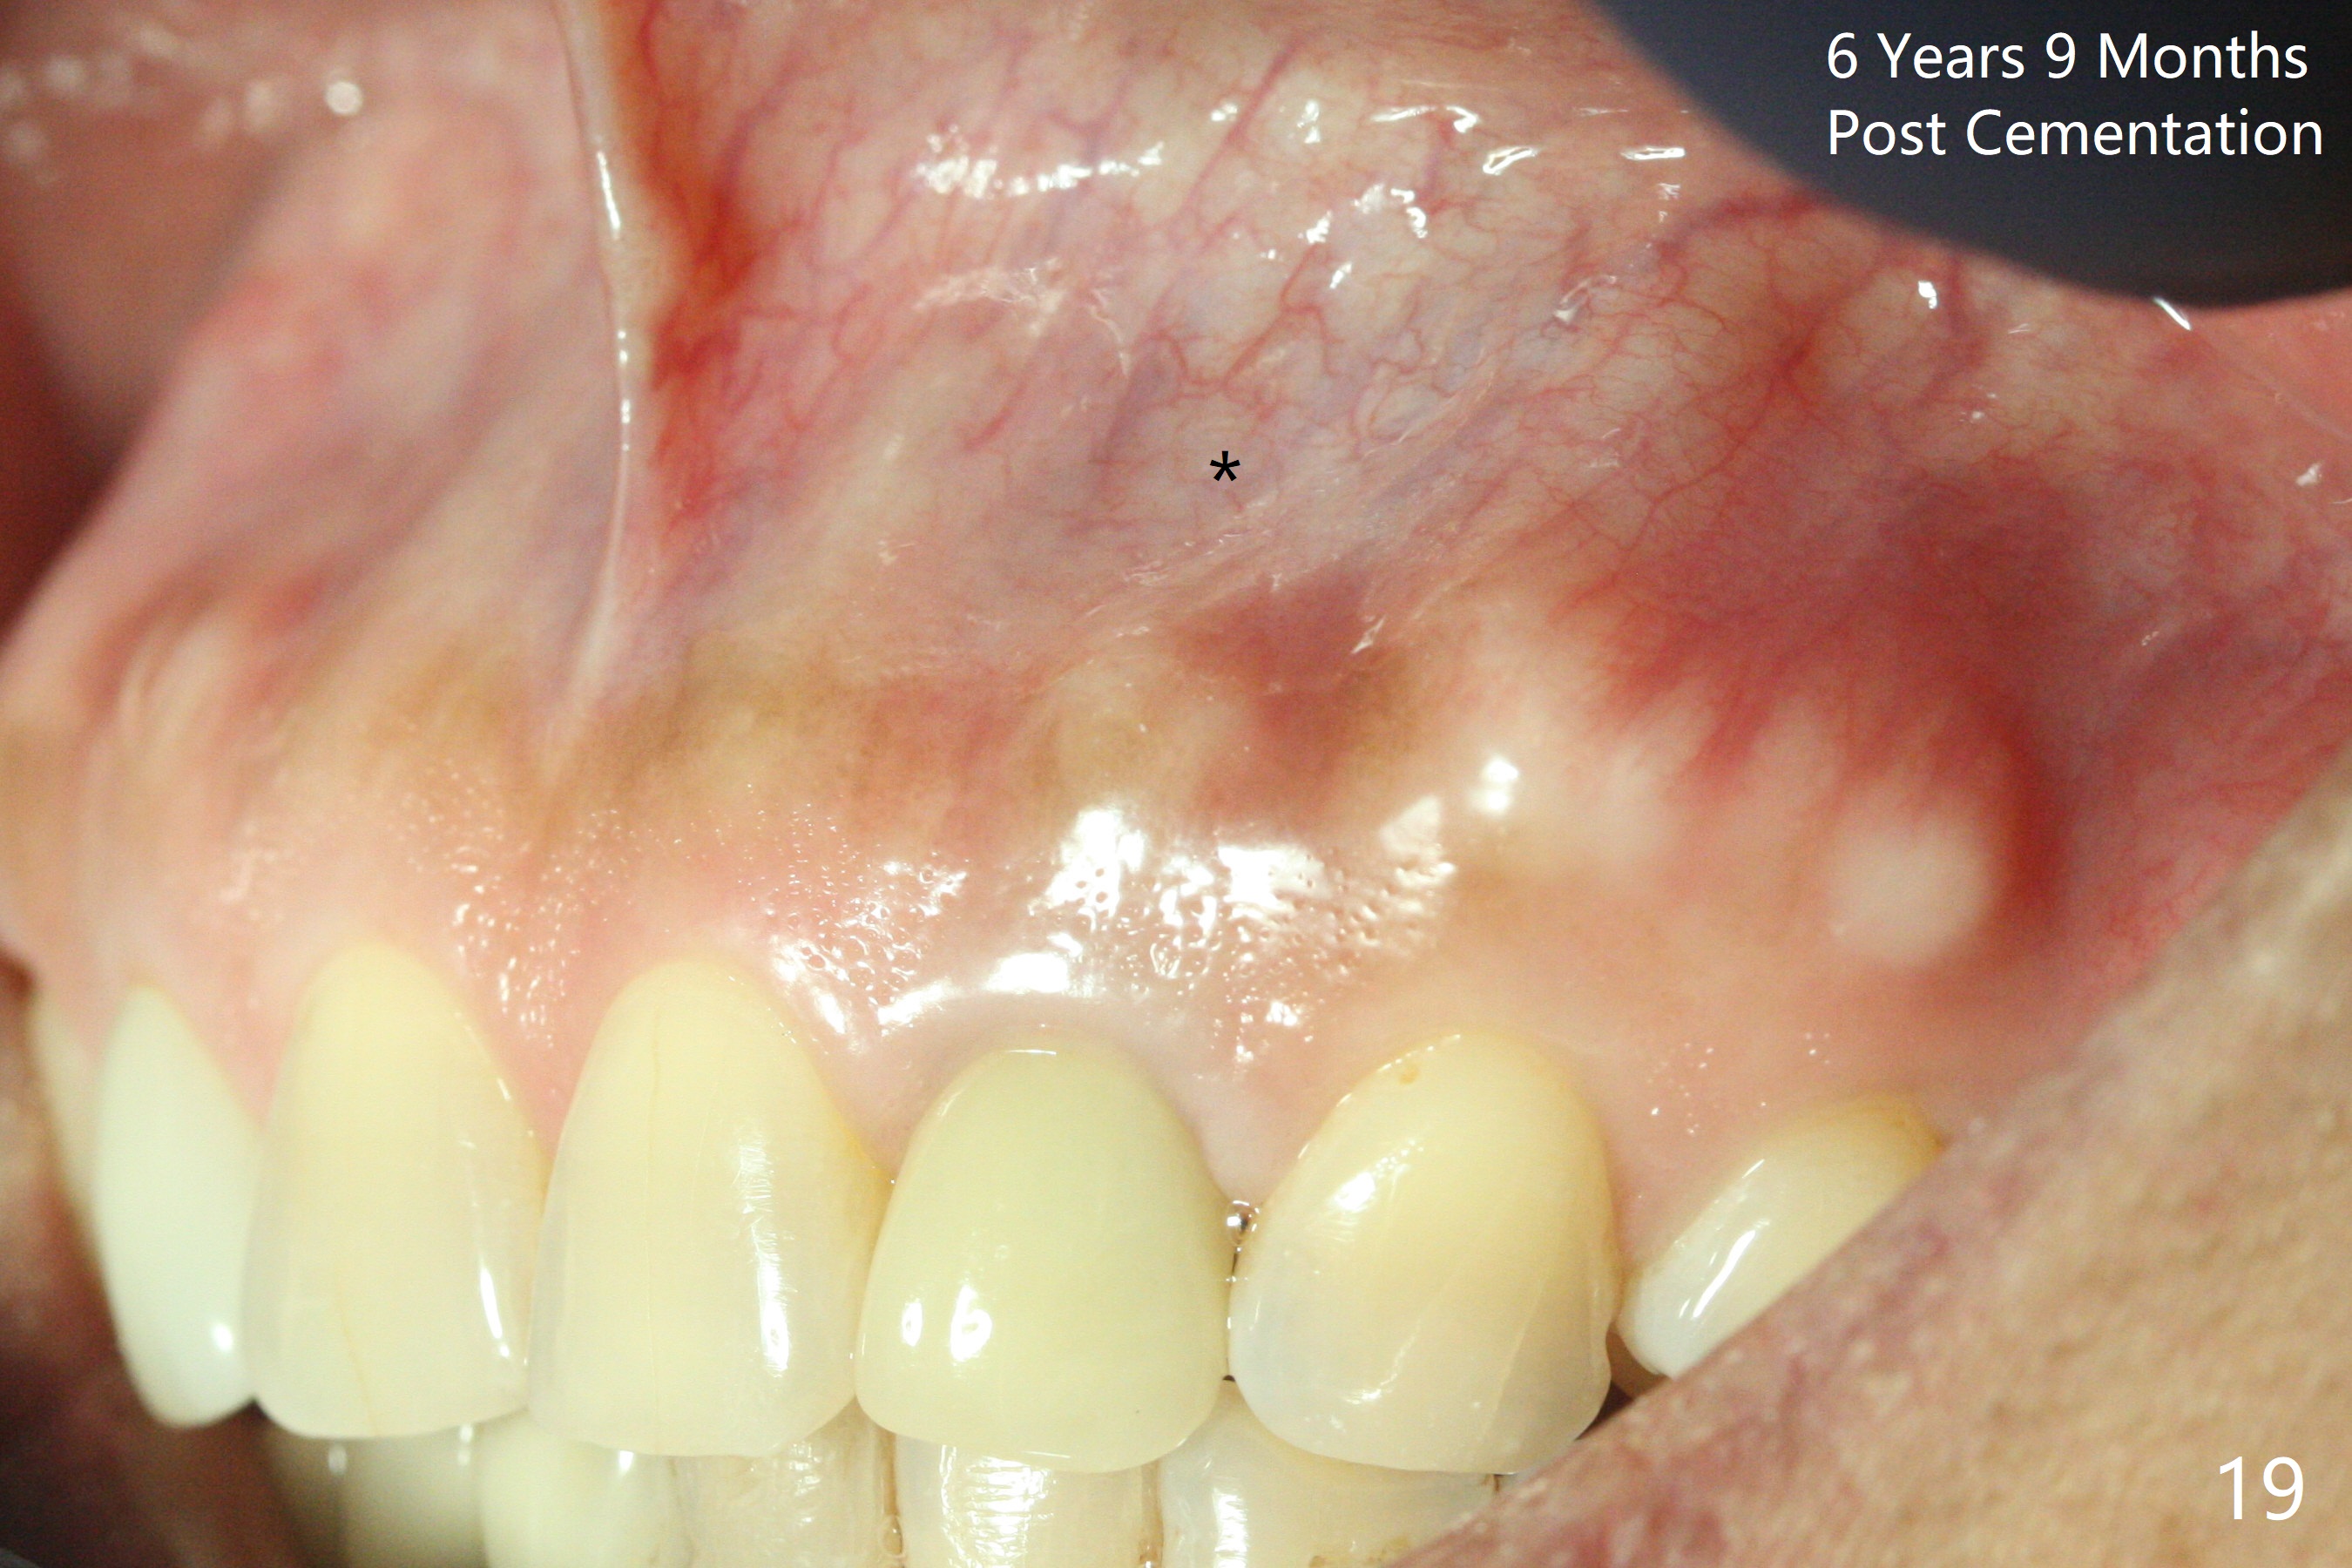

Dense bone forms immediately next to the implant 3 years 5 months post cementation (Fig.13) without gingival recession (Fig.14,15). In fact, the buccal plate maintains root contour over the implant (Fig.15 *). The root prominence remains 6 years 3 months post cementation (Fig.16-18 *). Appreciate the labial concavity associated with implant placement 6 years 9 months post cementation (Fig.19). The implant must have been placed quite palatal.